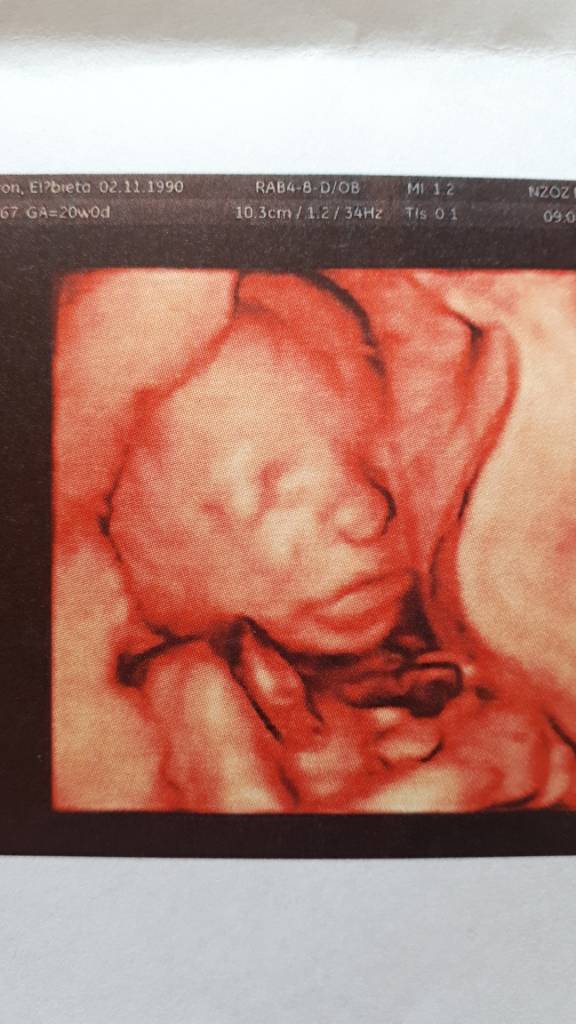

) o wow kolejna ciąża [emoji85][emoji3531] Gratulacje! :* Mi nie pobierał, miałam przed samą ciąża pobieraną.